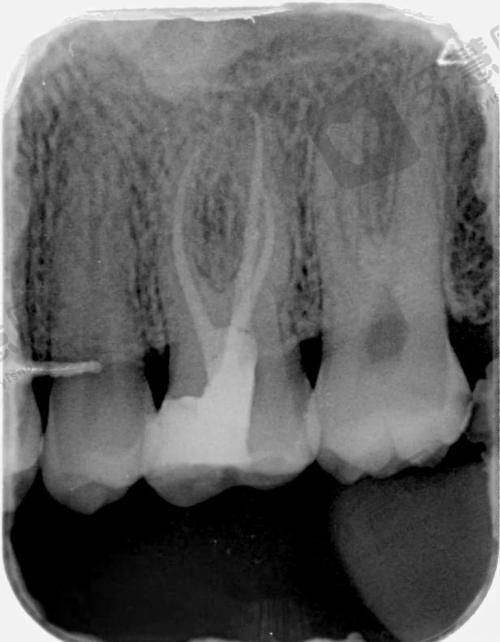

白若飞医生专精能力出色,在口腔领域有着广泛且深入的专精技能。他擅长固定修复、活动修复、种植修复、咬合重建等多个方面。在美学修复上,前牙全瓷贴面美学修复、全瓷冠的美学修复以及牙齿美白都展现出不错技艺,能有效改善患者牙齿外观。对于复杂牙周病、牙体牙髓、疑难根管治疗等病症,他凭借丰富的经验和专精知识,为患者提供精细治疗。此外,微痛拔牙、补牙、系统全方面洁牙以及儿童龋病、牙髓病的治疗也十分擅长,诊疗成效显著,深受患者信赖。